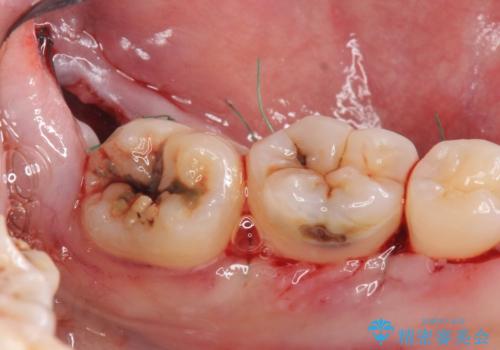

歯冠長延長術をおこなったアプローチの難しい虫歯治療

- 親知らずの抜歯を希望され来院されましたが手前の大臼歯2本に虫歯が認められ、治療が必要な状態でした。

クラウン形態にするには歯の高さが足りず設計できないため、親知らずの抜歯と共に歯周外科を同時に行うことで安定した歯周組織を獲得しセラミック治療を行う治療計画としました。

歯冠長の延長を行ったことで、安定したクラウン治療を行うことができました。